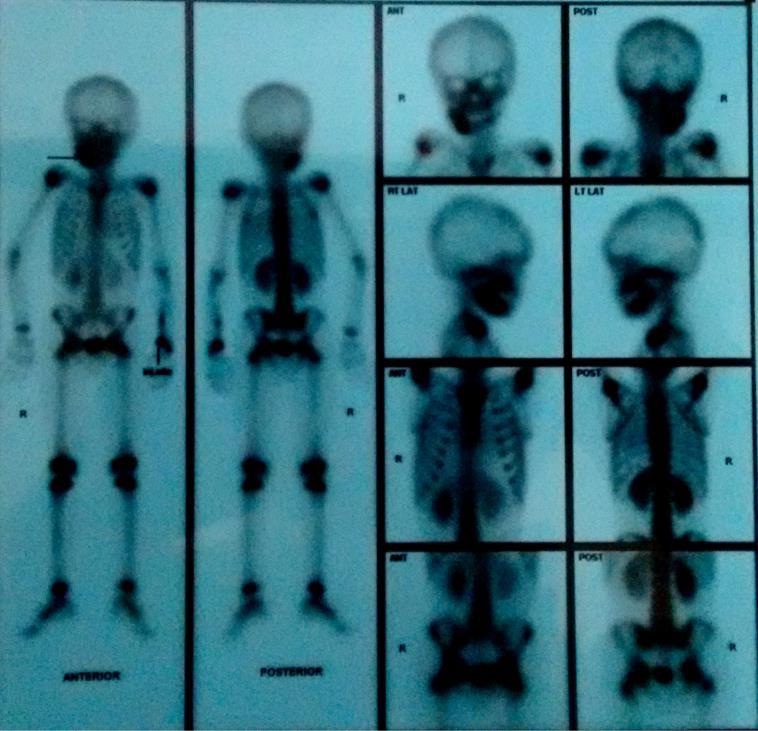

A five-year-old child patient came with a chief complaint of intermittent pain on the lower right side of the face since one month duration. Swelling was small in size and gradually increased to present size. On extra-oral examination, a localized swelling measuring approximately 4x5cm extending anteriorly from the right commissure of the lip up to the angle of mandible. Inferiorly up to the lower border of the mandible [Table/Fig-1]. Lymph node examination revealed two palpable submandibular lymph nodes on the right side which were mobile and tender on palpation. Intra-oral examination presented with restricted mouth opening with inter-incisal opening of 1.5cm and an ovoid solitary swelling in relation to the right buccal sulcus in relation to 43 to an erupting 47 extending till the retro-molar trigone which was tender on palpation [Table/Fig-2]. On bimanual palpation, expansion of the buccal and lingual plate was present. Orthopantomogram (OPG) and Cone Beam Computerized Tomogram (CBCT) revealed an ill-defined radiolucency from the mesial root of 46 to the ascending ramus with expansion of the lower border of the mandible [Table/Fig-3]. To diagnose the involvement of other systems in this triad a diagnostic 99 TC-MDP whole body scintigraphy was performed. The scintigraphy showed an increase tracer pooling in the right side of the mandible with no evidence of bony metastasis at other sites of the body [Table/Fig-4]. An incisional biopsy was deferred as the patient was uncooperative to local anaesthetic procedure. Patient was taken up for localized lesion enucleation, bone curettage and extraction of the tooth germ (46 and 47) with excision of the right submandibular lymph node. Under general anaesthesia, right Risdon’s submandibular incision was placed and layer by layer dissection was performed to reach the submandibular region [Table/Fig-5]. The submandibular lymph node was removed. Facial artery was ligated and the lower border of the mandible was reached. The lesion was identified and enucleated. Peripheral ostectomy was done for the adjacent bone along with removal of 47 tooth follicle [Table/Fig-6]. Haemostasis was obtained. The curetted specimen was sent for histopathological analysis which was suggestive of solitary eosinophilic granuloma [Table/Fig-7a]. For confirmatory diagnosis, an immunohistochemistry was performed which showed CD 1A immunoreactive in the tumour cells correlating with Langerhans Cell Histiocytosis (LCH) [Table/Fig-7b]. Post-operatively, patient was treated with the Tablet Indomethacin 300 mg BD regimen for a period of 2 months. Radiotherapy was deferred due refusal of the parents. He was periodically observed for a year and showed no evidence of recurrence till date. A one year post-operative OPG showed good wound healing with no signs of recurrence of the lesion [Table/Fig-8].

A 99 TC-MDP whole body scintigraphy showing an increase tracer pooling in the right side of the mandible with no evidence of bony metastasis at other sites of the body.